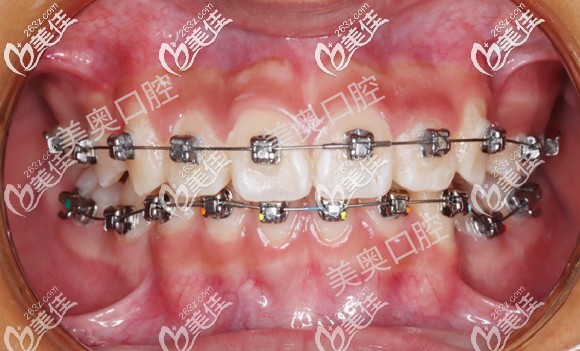

歷時(shí)22個(gè)月,男孩的上下牙列排齊整平,磨牙關(guān)系基本正常,拆除矯治器,進(jìn)入保持器保持階段,當(dāng)然,還需定期復(fù)查。